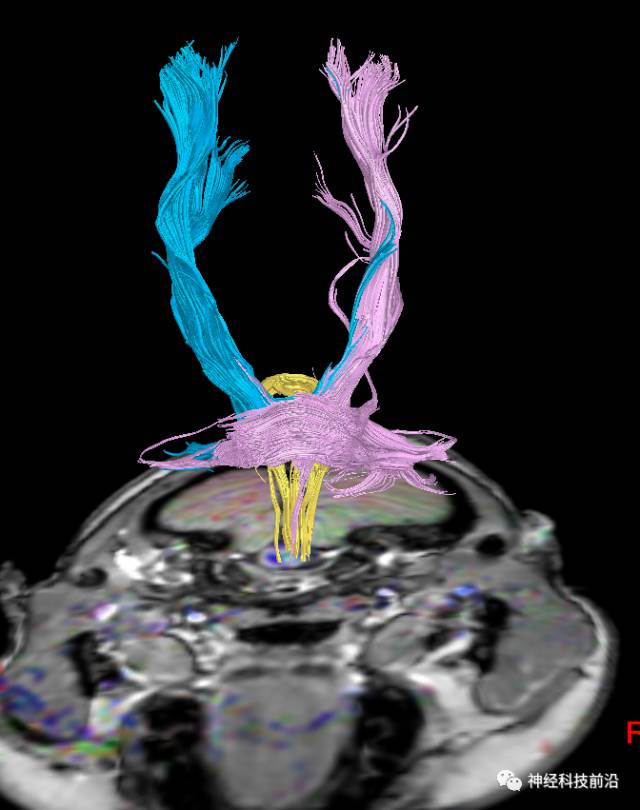

皮质脊髓束与皮质脑桥束的关系毗邻

上述纤维束与小脑中脚的位置毗邻

终上所述:脑干高信号为一近环形纤维束,内囊后肢高信号为皮质脑桥束,皮质脊髓束在中脑位置略靠后。高信号位于中脑前缘,是皮质脑桥束的位置所在,另外有部分桥连纤维。